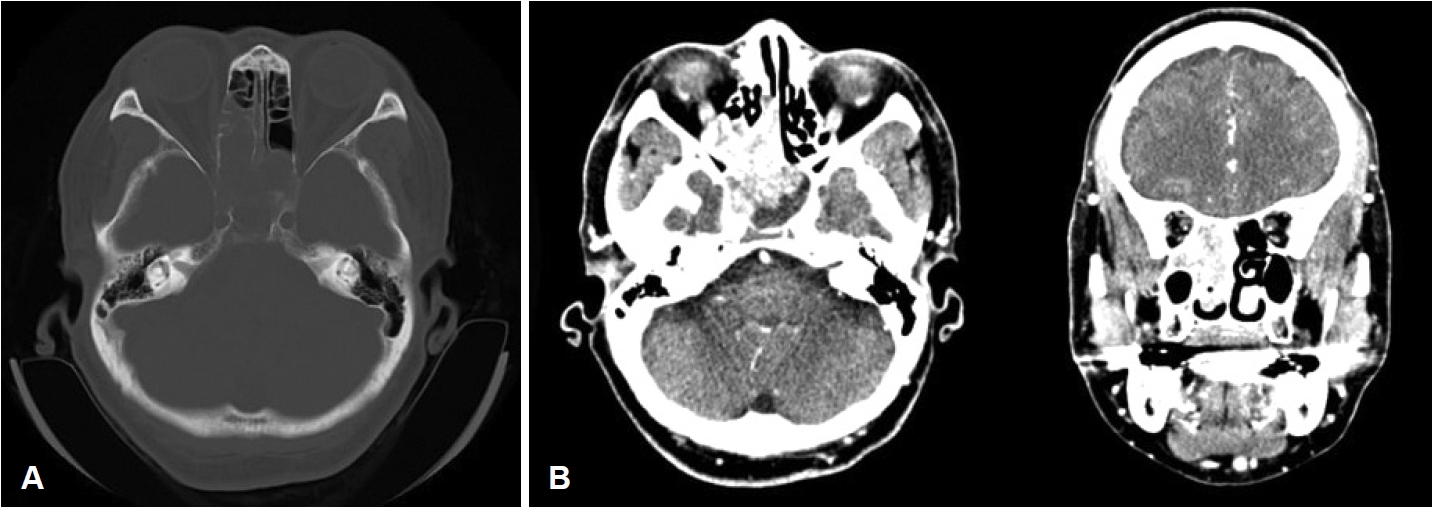

MRI scan findings were consistent with an intermediate signal on T1-weighted image (Fig. 2A), and heterogenous signal which includes presence of flow voids on T2-weighted image (Fig. 2B). Heterogenous enhancement was shown on contrast-enhanced T1-weighted image (Fig. 2C). Enhanced facial CT showed a 4 cm enhancing solid mass involving the right posterior nasal cavity, extending into the right ethmoid sinus and right sphenoid sinus, with evidence of bony erosion (Fig. 3). The left sphenoid sinus exhibited a non-enhancing mucoid density suggestive of sinusitis. Based on the imaging findings, the lesion was more consistent with an angiofibroma. Surgical treatment was decided accordingly.

Fig. 1.Endoscopic examination of right nasal cavity of the patient. A: Preoperative: a polypoid, whitish colored and solid mass found in the right nasal cavity, occupying between nasal septum and middle turbinate and extending to posterior nasal cavity. B: Postoperative 4 years: no residual mass or recurrence is found in the right sphenoid sinus. Fig. 2.Preoperative MRI images of the patient. A: T1-weighted image showed nasal cavity mass consistent with an intermediate signal. B: Heterogenous signal which includes presence of flow voids on T2-weighted image. C: Heterogenous enhancement was shown on contrast-enhanced T1-weighted image. Fig. 3.Preoperative enhanced facial CT images of the patient. A: Bony erosion of right lateral nasal wall by mass is shown in bone setting view. B: Both axial and coronal view show about 4 cm sized enhancing mass in right ethmoid sinus and sphenoid sinus. Fig. 4.Preoperative angiography. A: Through angiogram selected by right internal maxillary artery, hypervascular staining (red arrow) of right nasal cavity was shown. B: Hypervascular staining of right internal maxillary artery disappeared after embolization (blue arrow). Fig. 5.Microscopic features of permanent biopsy (hematoxylin and eosin stain, ×40). A: Sinonasal papilloma with inverted growth pattern. B: Various sizes of vascular spaces, ranging from dilated branching vessel to slit-like capillaries filled with fibrinous thrombin and edematous to collagenous stroma which indicates angiofibroma. REFERENCES2. Lisan Q, Laccourreye O, Bonfils P. Sinonasal inverted papilloma: from diagnosis to treatment. Eur Ann Otorhinolaryngol Head Neck Dis 2016;133(5):337-41.